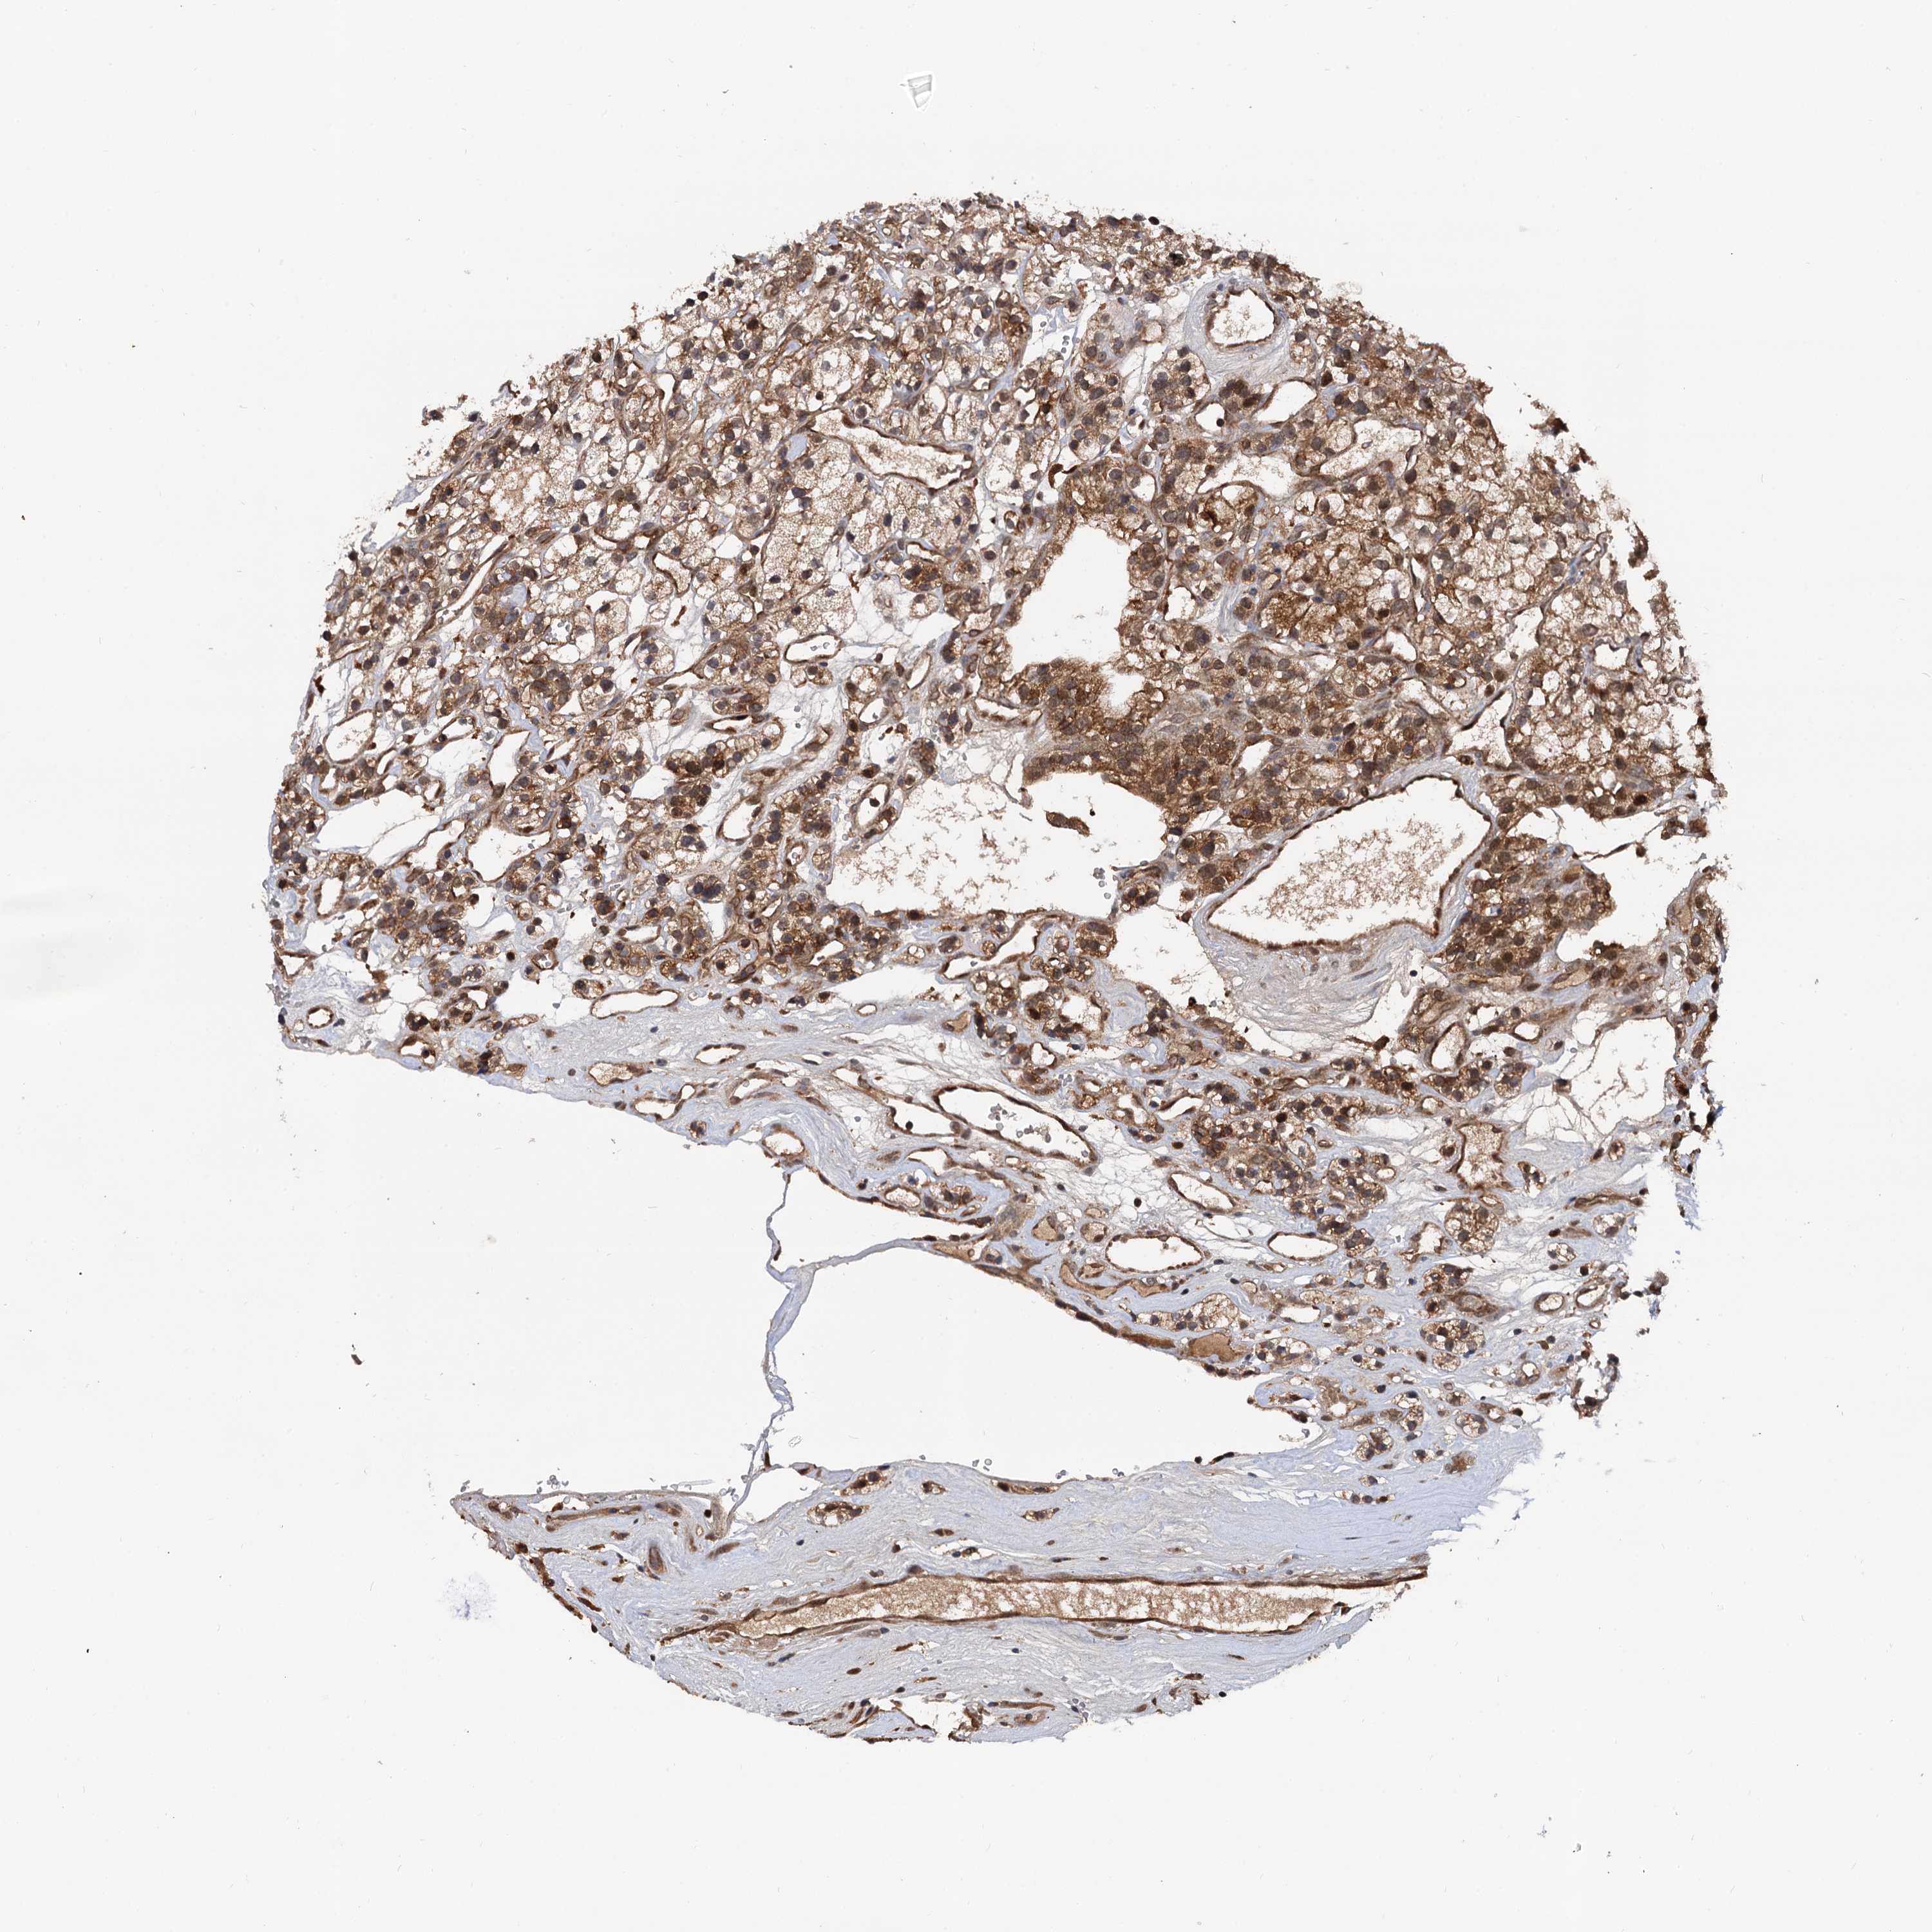

KIDNEY RENAL CLEAR CELL CARCINOMA (VALIDATION) - Interactive survival scatter ploti

The Survival Scatter plot shows the clinical status (i.e. dead or alive) for all individuals in the patient cohort, based on the same data that underlies the corresponding Kaplan-Meier plots. Patients that are alive at last time for follow-up are shown in blue and patients who have died during the study are shown in red.

The x-axis shows the expression levels (FPKM) of the investigated gene in the tumor tissue at the time of diagnosis. The y-axis shows the follow-up time after diagnosis (years). Both axes are complimented with kernel density curves demonstrating the data density over the axes. The top density plot shows the expression levels (FPKM) distribution among dead (red) and alive patients (blue). The right density plot shows the data density of the survived years of dead patients with high and low expression levels respectively, stratified using the cutoff indicated by the vertical dashed line through the Survival Scatter plot. This cutoff is automatically defined based on the FPKM cutoff that minimizes the p-score. The cutoff can be changed by dragging the vertical line or by entering a cutoff value in the square labeled "Current cut-off".

Under the Survival Scatter plot the p-score landscape (black curve; left axis) is shown together with dead median separation (red curve; right axis). Dead median separation is the difference in median mRNA expression between patients who have died with high and low expression, respectively. It is calculated as follows: median FPKM expression of dead patients with high expression - median FPKM expression of dead patients with low expression. This is intended to aid the user in visually exploring custom cutoffs and the associated p-scores and dead median separation.

Individual patient data is displayed and can be filtered by clicking on one or more of the category buttons on the top of the page. Categories describing expression level and patient information include: high, low, alive, dead, female, male and tumor stages. The scale of the x-axis can be toggled between linear and log-scale by clicking on the "x log" button. Mouse-over function shows TCGA ID, patient information and mRNA expression (FPKM) for each patient.

& Survival analysisi

Kaplan-Meier plots summarize results from analysis of correlation between mRNA expression level and patient survival. Patients were divided based on level of expression into one of the two groups "low" (under cut off) or "high" (over cut off). X-axis shows time for survival (years) and y-axis shows the probability of survival, where 1.0 corresponds to 100 percent.

SELENOP is validated prognostic, high expression is favorable in Kidney Renal Clear Cell Carcinoma (validation)

: 283.67

Average pTPM 601.6

Number of samples 100